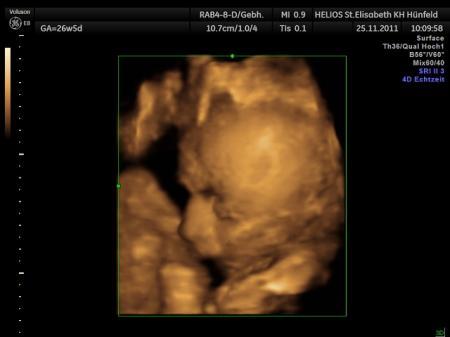

Bild zu babybauch angemalt. - Forum für Februar - Mamis